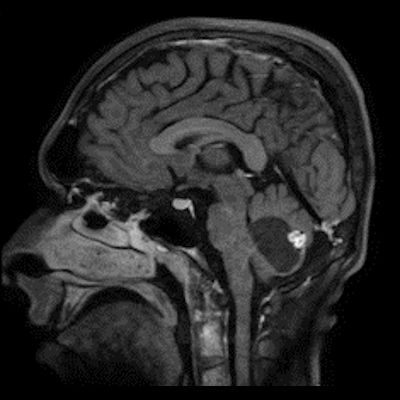

- B) Beyin MRG incelemesinde; 4. ventriküle bası etkisi oluşturan yaklaşık 3.5 cm boyutta, T2A hiperintens T1A hipointens kistik komponent (oklar) ve posteriorunda T1 ve T2A serilerde parankim ile izointens, içerisinde flow void alanların (oklar) izlendiği, post kontrast görüntülerde yoğun kontrast tutulumu gösteren mural nodül (oklar) barındıran düzgün sınırlı lezyon izlenmektedir.